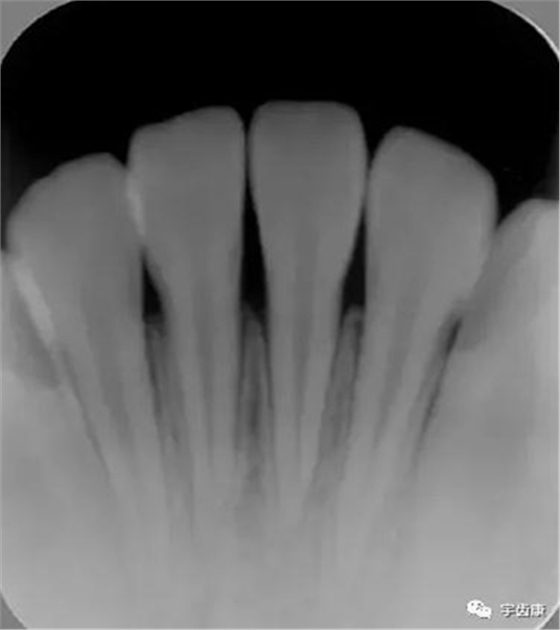

X線閱片知識(shí)